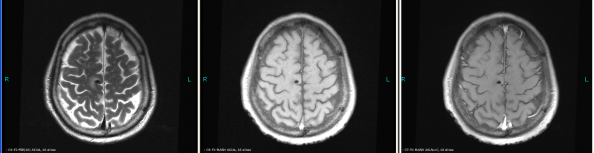

A 66-year old male patient with a smoking history was received by the Outpatient Department on September 14, 2015 due to “coughing for more than one month”. Main symptoms included a dry cough, a small amount of white phlegm, but freedom from fever, chest pains, bloody sputum, and any other discomfort. Stage IV-lung cancer is associated with anorexia and a loss of nearly 10 pounds. The patient had a poor constitution in the past, with a history of “acute hepatitis”, “type-2 diabetes” and “obsolete pulmonary tuberculosis”. The patient was accepted in the Department of Respiratory Medicine on September 15. The results of a lung CT scan indicated a “space occupied for posterior basal segment of right inferior lung and enlarged for mediastinal lymph nodes”. The patient was approved for a CT- guided transthoracic needle biopsy, immunohistochemistry, EGFR gene mutation detection, and systemic metastases assessment. He was diagnosed as “primary lung cancer, right lung adenocarcinoma, T4N3M1B (lung, pleura and brain), and stage-IV EGFR Exon 19 deletion mutation (Fig. 1A and Fig. 2A)”.

The patient checked for further treatment on November 23, 2015. A pre-chemotherapy assessment was made and the results showed multiple bone metastases and multiple enlarged lymph nodes in the left shoulder blade, the fourth lumbar, the right iliac bone and other locations. Performance status (PS) was only one point. Pemetrexed Disodium (500 mg/m2 d1) + Carboplatin (AUC 5 d1) + Bevacizumab (7.5 mg/Kg d1) was administered beginning November 26, 2015 for the chemotherapy treatment and supportive therapy was provided, such as, dehydration, reduction of intracranial pressure, promotion of bone repair, pain relief, and waist protection. After discharge, the coughing basically disappeared and the dizziness, backaches, and hemiparesthesia of the left side were significantly improved. Patient emotional state and sleep quality was significantly improved. It was basically normal after a routine blood examination. A second chemotherapy treatment was successfully completed on December 18 (the program is idem). The patient returned to the hospital on January 6, 2016 and was proposed for a third chemotherapy. The pre-chemotherapy assessment showed that the measurable, targeted right lung lesion had decreased (3.2 mm, with a rate of decrease 44.8 %) (Fig. 1D). Lymphangitis carcinomatosa was significantly decreased and right frontal nodulus lesions were reduced significantly (Fig. 2C). No new lesions were found. Efficacy was assessed as partial relief (PR). A third and fourth chemotherapies were completed on January 9 and January 30, 2016. Efficacy was re-assessed as PR (Fig. 1E) with lung CT review as an outpatient on February 11. Since then, the patient had been subjected to a combined administration program of pemetrexed disodium (500 mg/m2 d1) + bevacizumab (7.5 mg/Kg d1) for continued chemotherapy. A lung CT and a cranial MRI were peformed on April 16. The results showed that the control of lung lesions and intracranial lesions were basically the same as before (Fig.1F and Fig. 2D). The patient had no cough, backaches, or hemiparesthesia and the quality life significantly improved. PS was decreased to zero.